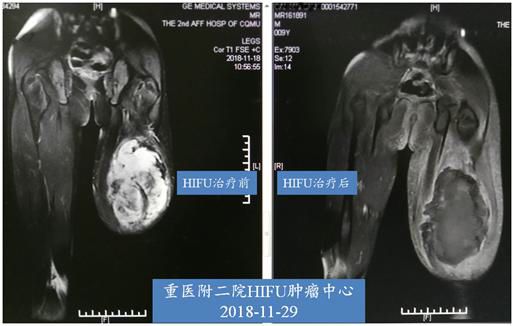

HIFU治疗前,MRI提示肿瘤组织血供丰富,强化明显;治疗后,提示无血供,绝大部分坏死,达到预期治疗目的。从此例病例中总结三点:第一,肢体软组织肉瘤恶性程度相对稍低,但手术切除后易局部复发,且损伤较大。HIFU治疗是一种无创治疗方法,经治疗后保留完好的支撑结构,保持了局部肢体的完整性;而坏死的肿瘤组织可经体内吸收、缩小;第二,这个疾病本身特性表现为局部易复发,较外科手术来讲,HIFU治疗有较好的重复性;第三,此患者为处于生长发育期孩童,HIFU治疗过程中已避开股骨,但肢体发育及功能的影响暂不能预估,需长时间观察患肢神经功能和生长情况,海扶治疗科也将按严格按计划随访。